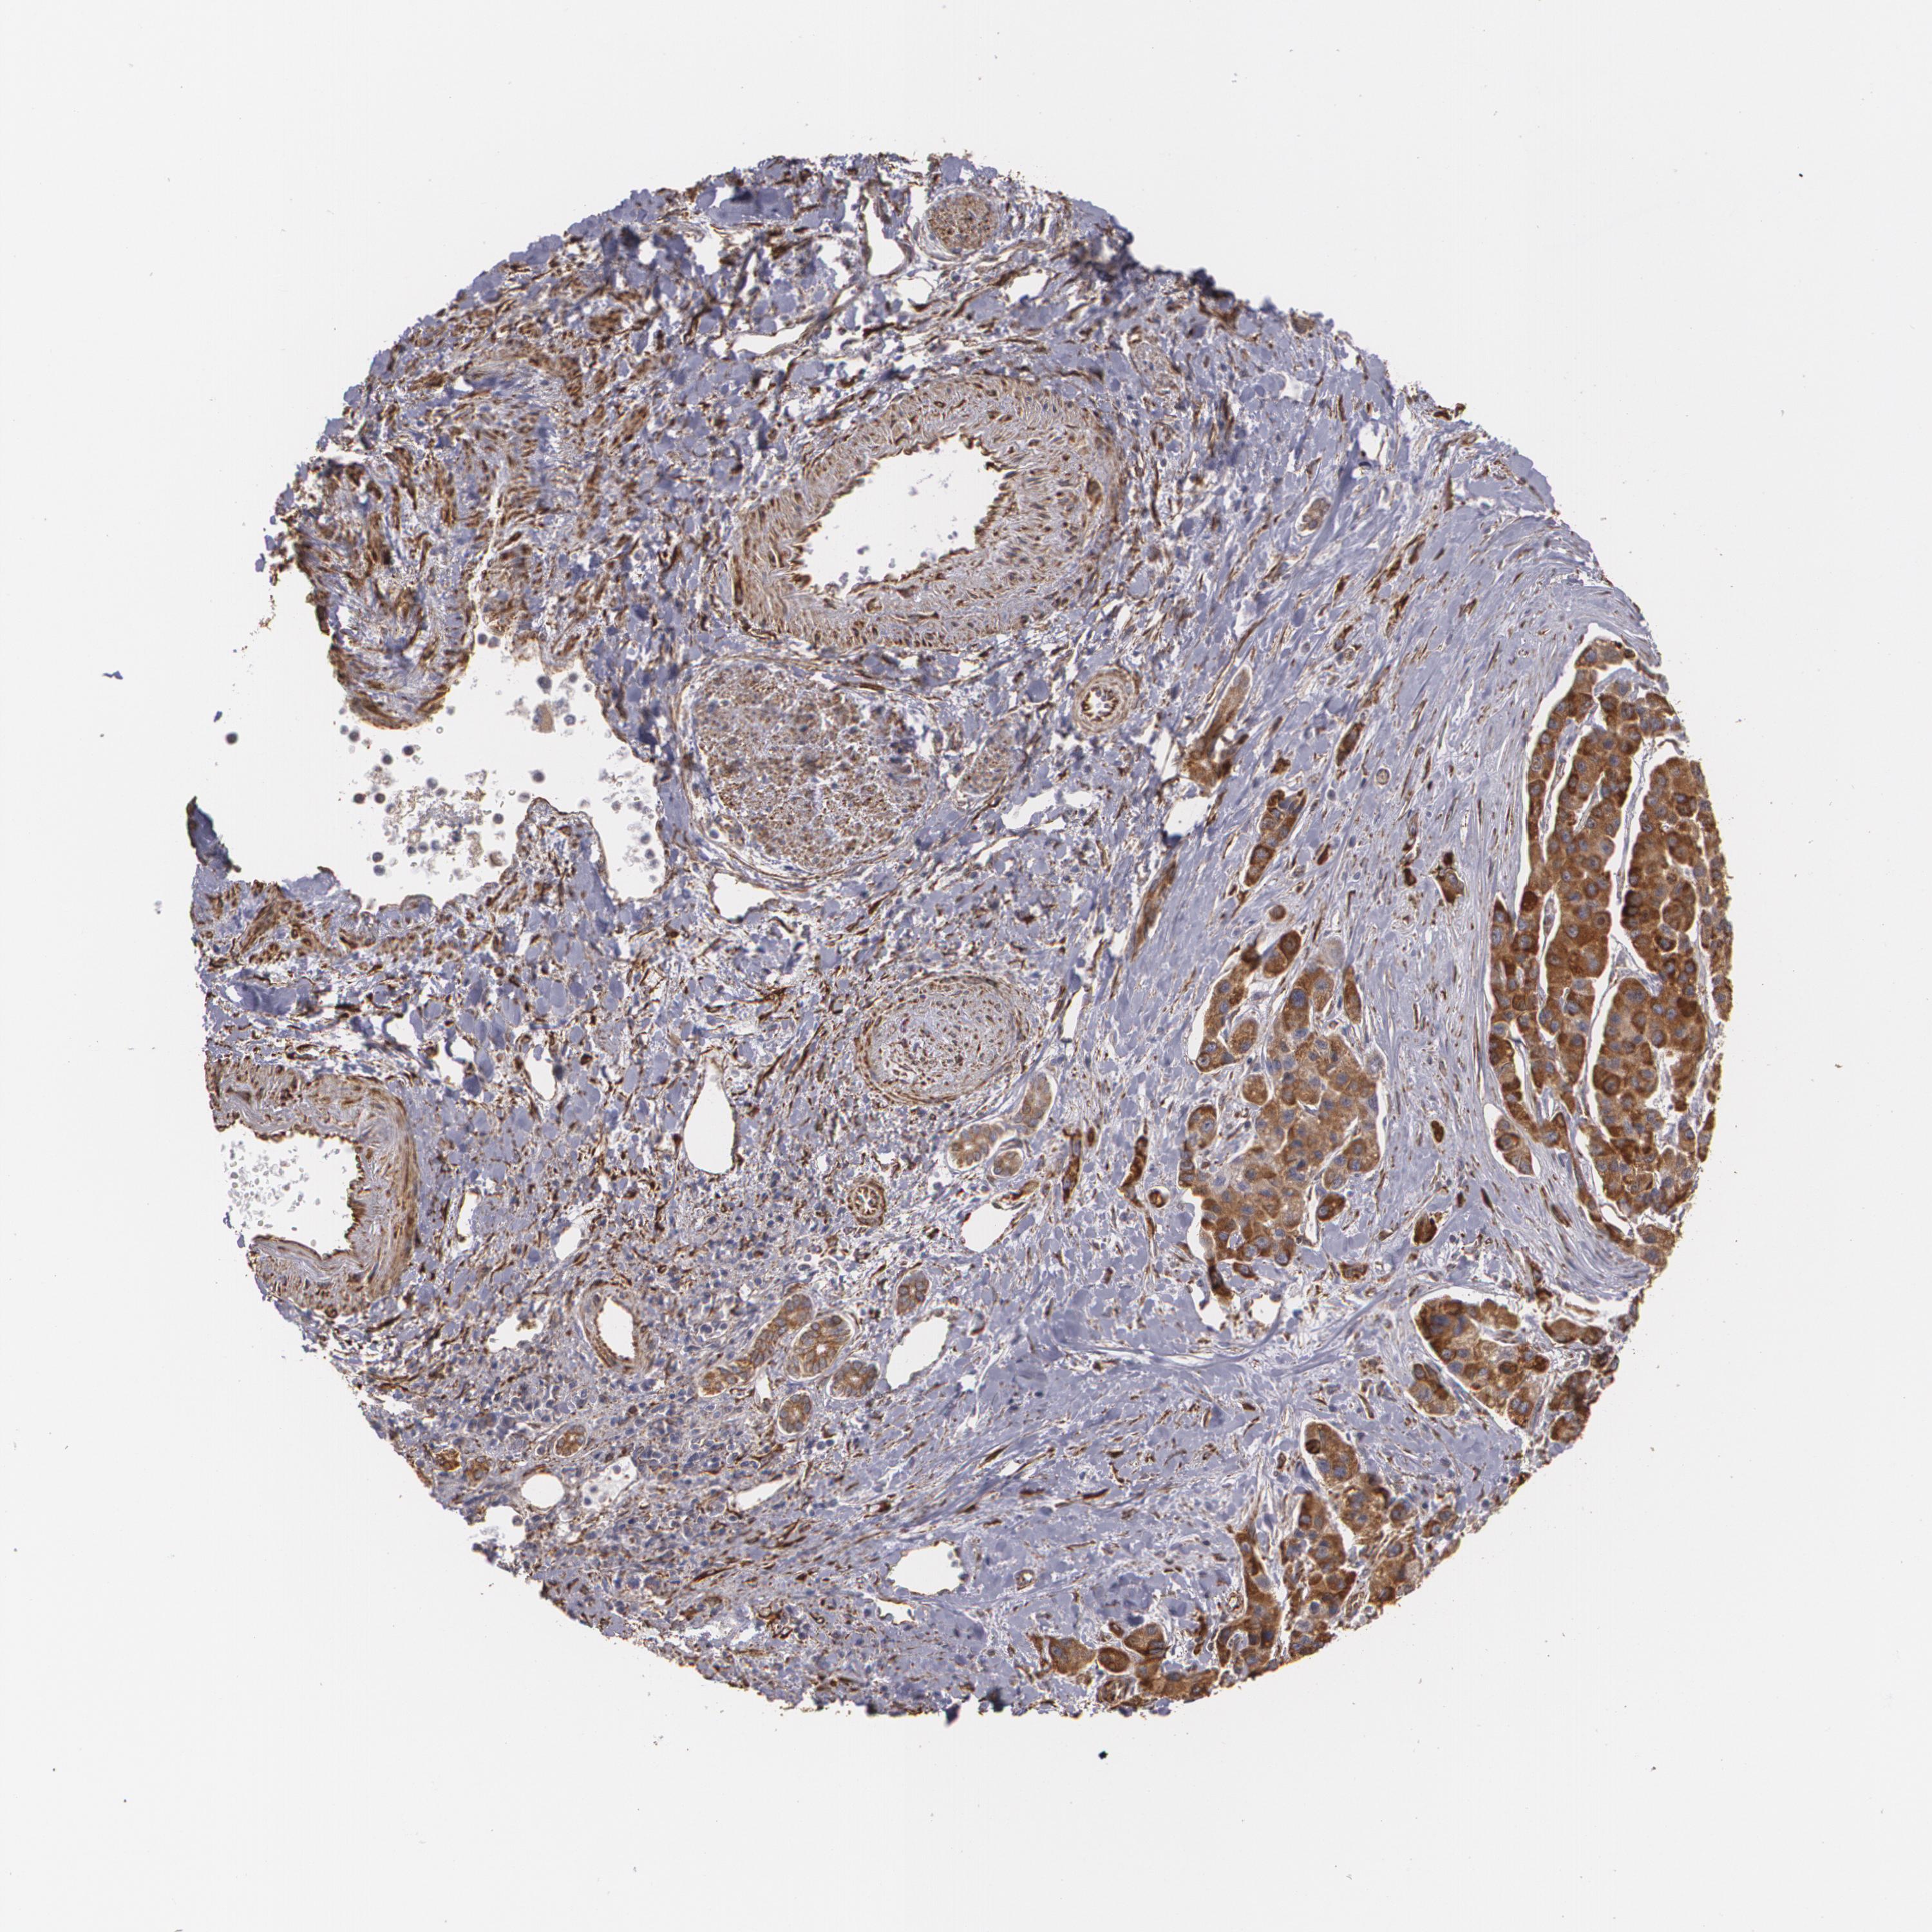

LIVER CANCER - Protein expressioni

A mouse-over function shows sample information and annotation data. Click on an image to view it in a full screen mode. Samples can be filtered based on level of antibody staining by selecting one or several of the following categories: high, medium, low and not detected. The assay and annotation is described here.

Note that samples used for immunohistochemistry by the Human Protein Atlas do not correspond to samples in the TCGA dataset.

Antibody stainingi

Antibody staining in the annotated cell types in the current human tissue is reported as not detected, low, medium, or high, based on conventional immunohistochemistry profiling in selected tissues. This score is based on the combination of the staining intensity and fraction of stained cells.

Each image is clickable and will lead to virtual microscopy that enables deeper exploration of all samples and also displays staining intensity scores, fraction scores and subcellular localization as well as patient and tissue information for each sample.

Antibody HPA001566

Staining

High

Medium

Low

Not detected

Intensity

Strong

Moderate

Weak

Negative

Quantity

>75%

75%-25%

<25%

None

Location

Nuclear

Cytoplasmic/membranous

Cytoplasmic/membranous,nuclear

Carcinoma, Hepatocellular, NOS